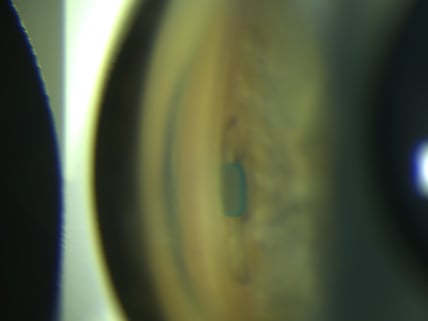

Der iStent Inject w ist das kleinste am Menschen zugelassene Implantat mit 0,4 mm Länge und 0,25 mm Breite und besteht aus Titan. Die winzigen Implantate werden direkt in den Abflusskanal (Schlemm-Kanal) eingesetzt. In der Regel werden pro Auge 2 Stents implantiert, die von außen nicht sichtbar sind. Mithilfe der iStents kann das Kammerwasser wieder besser abfließen und der Augeninnendruck wird gesenkt. Da keine Bindehauteröffnung nötig ist, hinterlässt der Eingriff kein Fremdkörpergefühl und wird in der Regel mit der Operation des grauen Stars kombiniert, es sind keine zusätzlichen Schnitte notwendig. Die Drucksenkung ist in Kombination mit der Operation des grauen Stars im mittleren Bereich und sollte so zu einer Reduktion der anzuwendenden drucksenkenden Augentropfen führen.